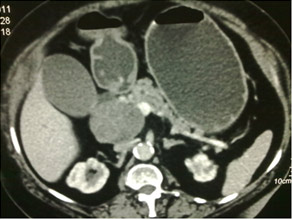

CT scan of Chronic pancreatitis with cancer (stent seen in the pancreatic duct, arrow pointing the tumor)

CT scan of chronic pancreatitis with large tumor, stones in the pancreatic duct

A continuing inflammatory process characterized by irreversible morphological change typically causing pain and loss of function. Common causes include chronic alcohol abuse, hyperlipidaemia, hypercalcaemia, malnutrition, tropical and idiopathic. Commonest mode of presentation is chronic pain (upper abdomen and back) and may be associated with Diabetes Mellitus and steatorrhoea (loose oily stools). Importantly pancreatic cancer may occur in 3%-18% of these patients. Surgery tackles pain & surrounding organ complications like duodenal and biliary obstruction secondary to a pancreatic head mass. Surgery varies from a simple pancreaticojejunostomy for Pancreatic duct drainage to the more complex head coring procedures (Frey’s and Beger’s procedure). The radical Whipple’s procedure is done when cancer cannot be ruled out.